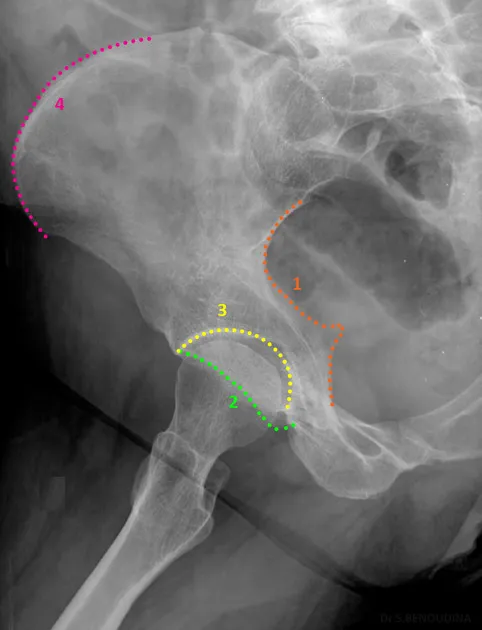

Special Views & Signs - Beyond the AP

- Judet Views (Oblique Pelvis): Used to evaluate acetabular & pelvic ring fractures. Two views (iliac and obturator oblique) named for the side rolled up.

- Iliac Oblique: Shows the posterior column and anterior rim.

- Obturator Oblique: Shows the anterior column and posterior rim.

- Inlet View: Assesses anteroposterior displacement of the pelvic ring. The beam is angled 40° caudally.

- Outlet View: Evaluates vertical displacement of the hemipelvis. The beam is angled 40° cephalad.